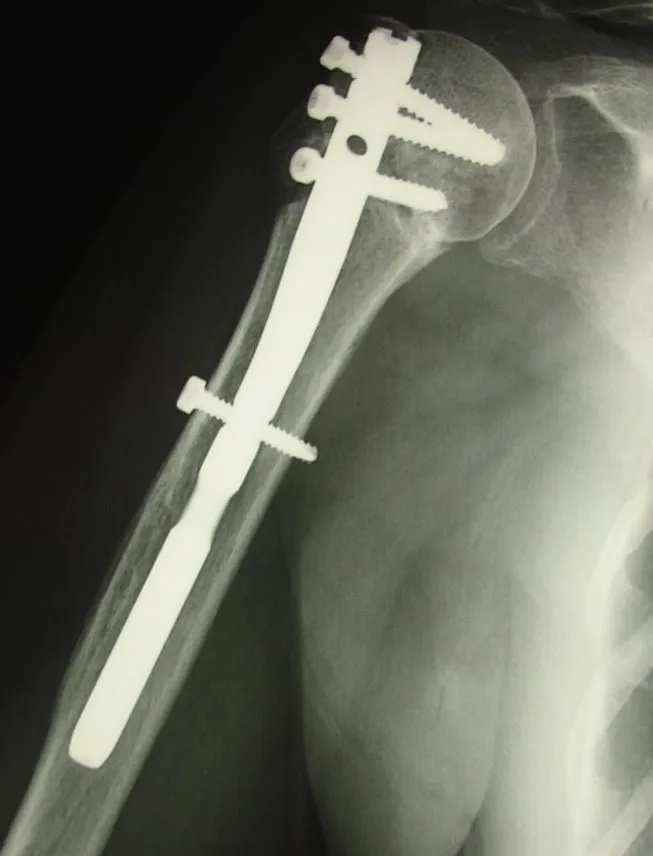

Le traitement chirurgical

Le traitement chirurgical sera adapté au type de fracture mais aussi au patient (âge, lésions préexistantes, état général et demande fonctionnelle).

Il consiste en la réalisation d'une ostéosynthèse (repositionnement et fixation des fragments osseux), le plus souvent par une plaque vissée. L'intervention est réalisée sous anesthésie générale, parfois associée à une anesthésie loco-régionale. Un contrôle radiographique per-opératoire permet au chirurgien d'avoir un contrôle parfait du positionnement du matériel.

Après l'intervention, le bras est immobilisé dans une attelle coude au corps pendant 4 à 6 semaines. La rééducation débute après 4 semaines chez un kinésithérapeute de ville.